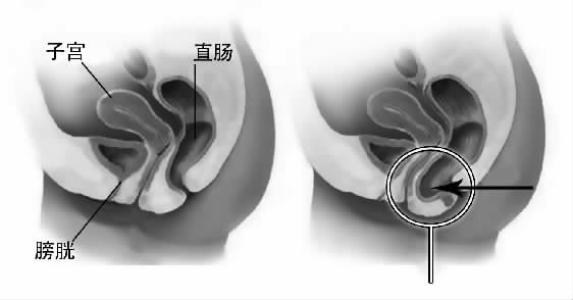

直肠前突(rectocele,RC)即直肠前壁突出,亦称直肠前膨出。是患者直肠阴道隔薄弱直肠前壁突入阴道内的一种病理状态,是排便困难的主要因素之一。

1.作排便动作时可见阴道后壁呈圆形或卵圆形膨出,会阴部组织向外膨出。

2.肛管直肠指诊在肛管上方的直肠前壁可扪及易突入阴道的薄弱区,重度者可将阴道后壁推至阴道外口。